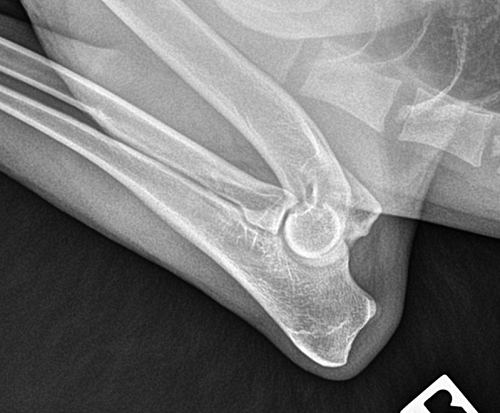

Elbows: OFA Normal